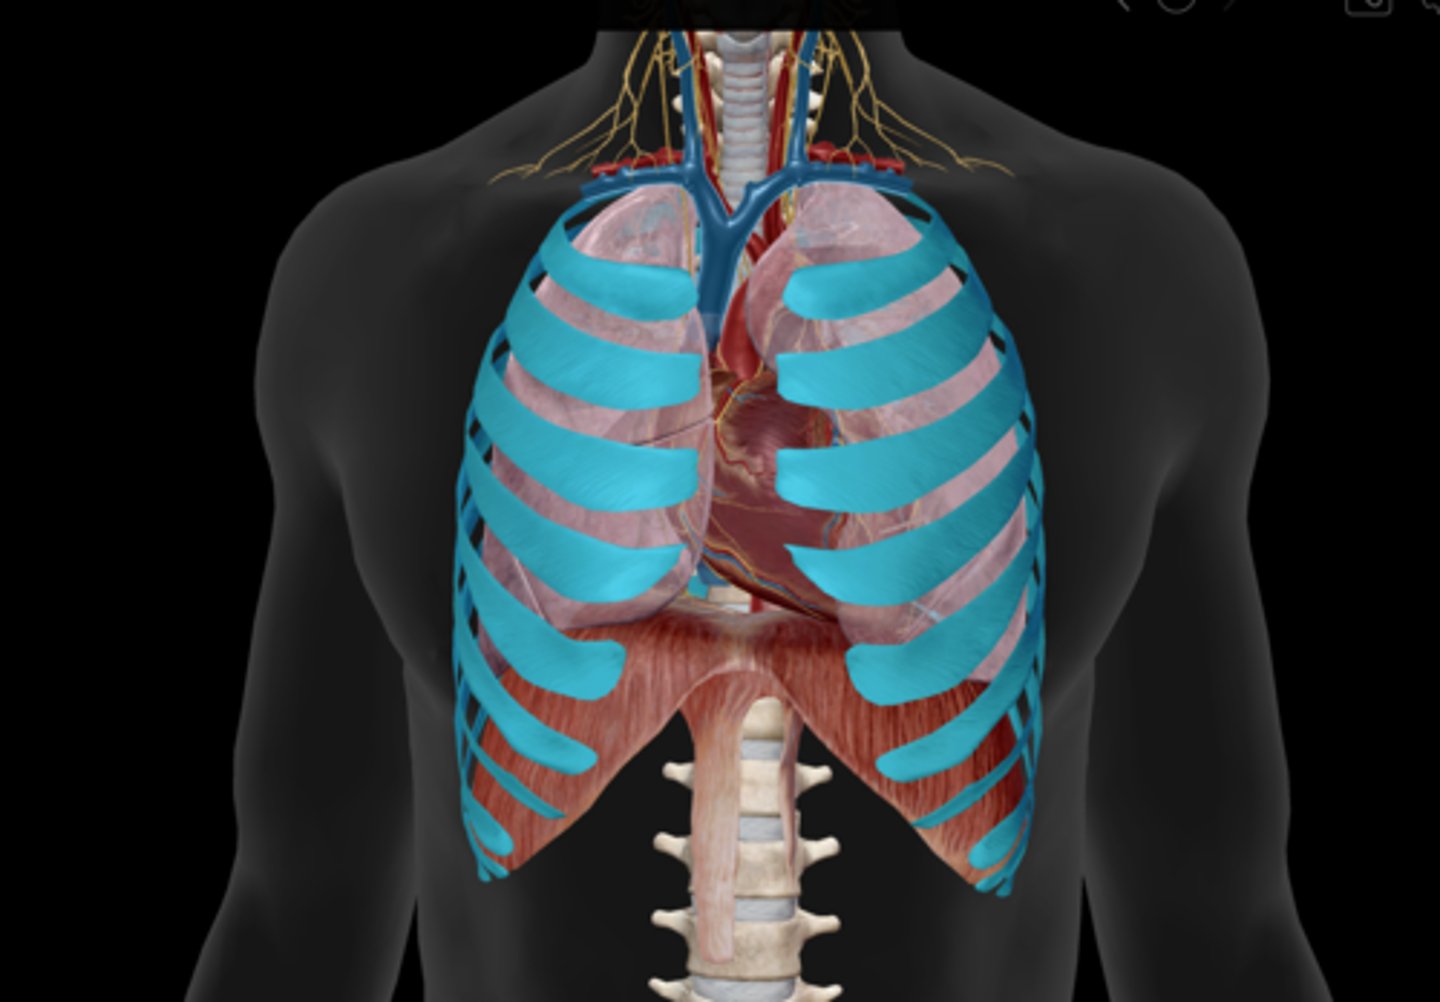

External intercostals

Internal intercostals